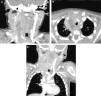

Se modifica tratamiento a cefotaxima y clindamicina intravenosas (por fallo de régimen previo y ampliar la cobertura de anaerobios), y se realiza TC cervical, destacando absceso desde rinofaringe hasta mediastino súpero-anterior (fig. 1A y B). El paciente se mantiene asintomático salvo edema laterocervical derecho y fiebre intermitente. Se decide actitud quirúrgica expectante dada la escasa sintomatología y el excelente estado general, y continuar tratamiento con cefotaxima (se retira clindamicina a las 24-48h por aparición de rash cutáneo). A las 72h, normalización casi completa del examen físico y desaparición de la fiebre. Se repite TC, observando disminución significativa del absceso (fig. 1C), junto con trombosis parcial de vena yugular interna derecha. Ante la buena evolución clínico-radiológica de la infección se decide no intervenir, iniciar tratamiento con heparina de bajo peso molecular y cambiar antibioterapia a amoxicilina-clavulánico (según últimas recomendaciones de la SEIP y la bibliografía más reciente para el tratamiento de abscesos cervicales), hasta completar 21 días de tratamiento parenteral. Al alta, tratamiento con amoxicilina-clavulánico oral (una semana) y heparina subcutánea durante 3 meses.

A) TAC con contraste, corte coronal cérvico-torácico. Absceso laterocervical derecho que acompaña al paquete vasculo-nervioso carotídeo, transcurre por espacio retrofaríngeo, y llega a mediastino súpero-anterior y medio. Secundariamente produce un colapso de la vena yugular interna derecha. B) TAC con contraste, corte axial a nivel de mediastino. Se observa como la colección se extiende hasta mediastino medio. C) TAC con contraste, corte coronal cérvico-torácico. Disminución del tamaño de la tumoración, permaneciendo solo una pequeña abscesificación laminar laterocervical y retrofaríngea, con otra fina colección en mediastino súpero-anterior. Se visualizan aun adenopatías laterocervicales y en mediastino. Además, destaca trombosis de la vena yugular interna derecha (se observa un segmento largo proximal que ha desaparecido, viéndose la región distal de esta).